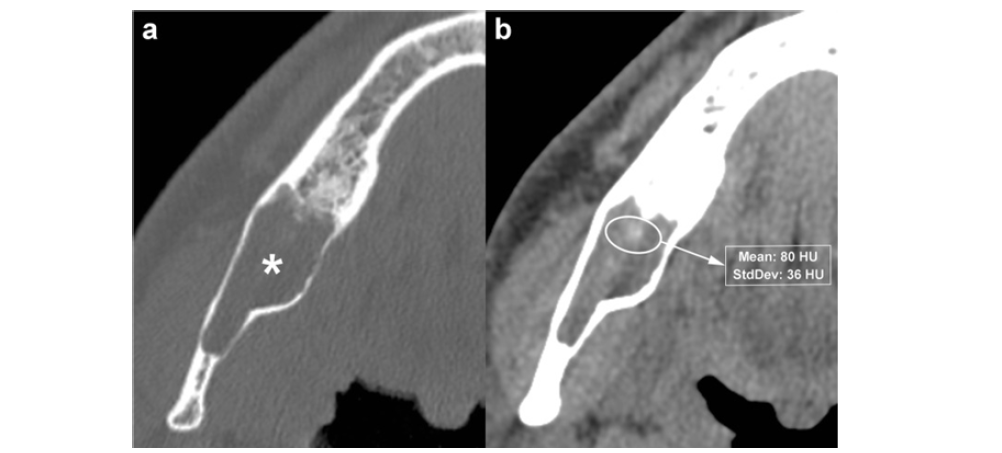

c Histological section shows the characteristic parakeratinised stratified squamous epithelial lining with a corrugated surface pattern (H&E, 10×). Panoramic CBCT imaging with a 20-mm slice thickness (a) reveals a multilocular OKC. On this reconstruction, septa appear to subdivide the lesion into multiple locules. Crosssectional CBCT images reconstructed at 0.5-mm thickness (b) demonstrate that several of these septa are complete (arrowheads), while others are incomplete (wavy arrows). Some of the small loculations observed on the panoramic reconstruction (black asterisk, white and black stars) actually represent a single, larger loculation with scalloped inner borders (Figure 8a). Compression and lingual displacement of the mandibular canal beneath the root of the third molar are also evident (opposing arrows). Curved arrow identifies the mandibular foramen; arrows indicate the mandibular canal. OKCs may be associated with an impacted tooth, a feature resembling that of a dentigerous cyst and observed more frequently in younger patients [14,15]. Internal highdensity foci are commonly present and correspond to keratinized material within the cystic cavity [14]. This characteristic internal appearance is more effectively demonstrated on MDCT because of its superior soft tissue contrast resolution compared with CBCT. Although uncommon, calcifications can occur within OKCs and are most often identified on histological evaluation (Figure 8b). On MDCT, OKCs typically show no appreciable enhancement following contrast administration.

Figure 8:Axial MDCT image with bone window (a) shows an OKC in the posterior region of the right mandible (asterisk). Axial MDCT image with soft tissue window (b) clearly demonstrates a high-density area within the lesion (elliptical ROI), with a mean attenuation value of 80 HU.

Panoramic (a) and axial (b) MDCT images depict an osteolytic lesion in the interforaminal region of the mandible, histologically confirmed as an OKC. The lesion causes expansion and thinning of the buccal cortex (arrowheads). Multiple punctate high-density foci consistent with calcifications are visible within the lesion (arrows), and one of these foci extends into the adjacent soft tissue (curved arrow). Dots indicate the mesial portion of the mandibular canal. (c) Histological images show the characteristic epithelial lining and calcifications (large black arrows) within the underlying connective tissue (H-E 10×).